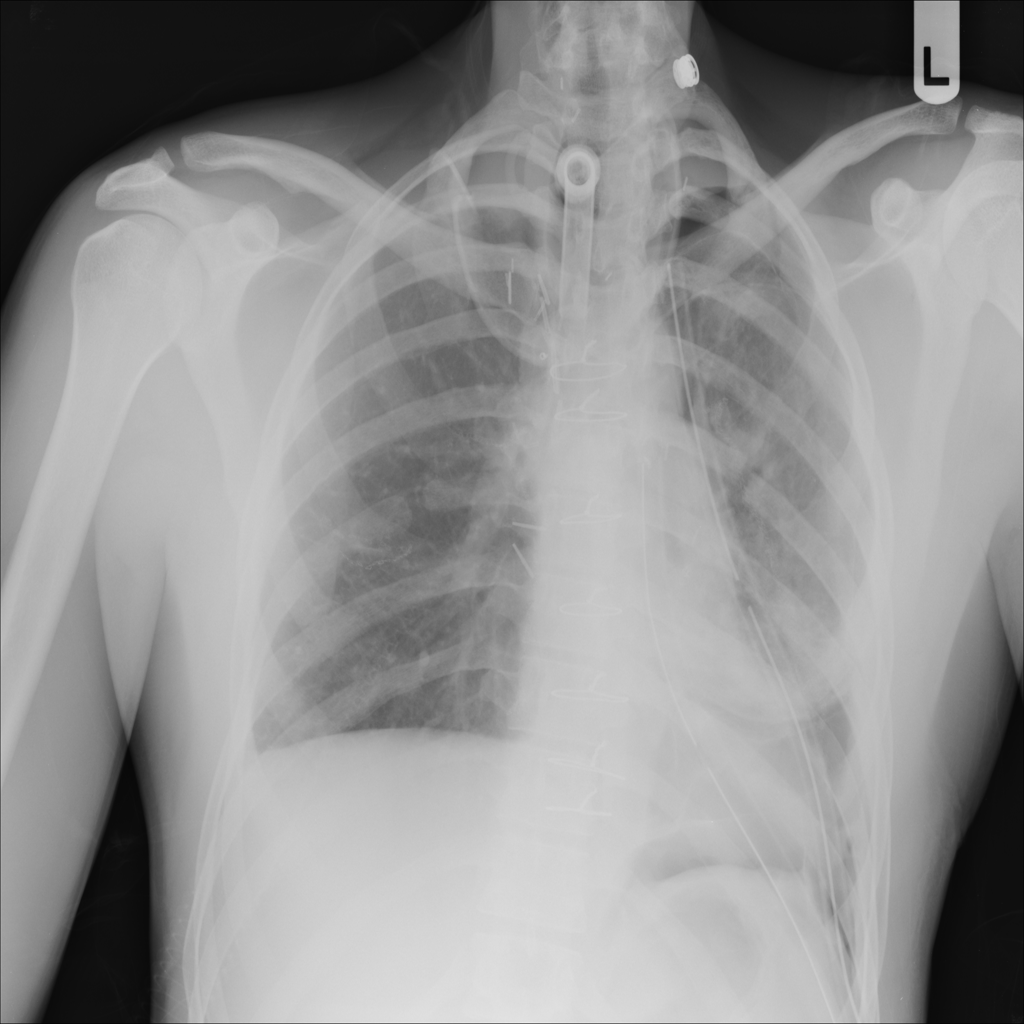

PAT-4639 · IMG-011Pneumothorax

PAT-4639 · IMG-011

AP